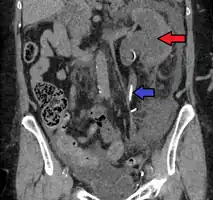

Left sided hydronephrosis in a person with an atrophic right kidney. Stent is also present (image below).

Left sided hydronephrosis, coronal view. Stent is also present.